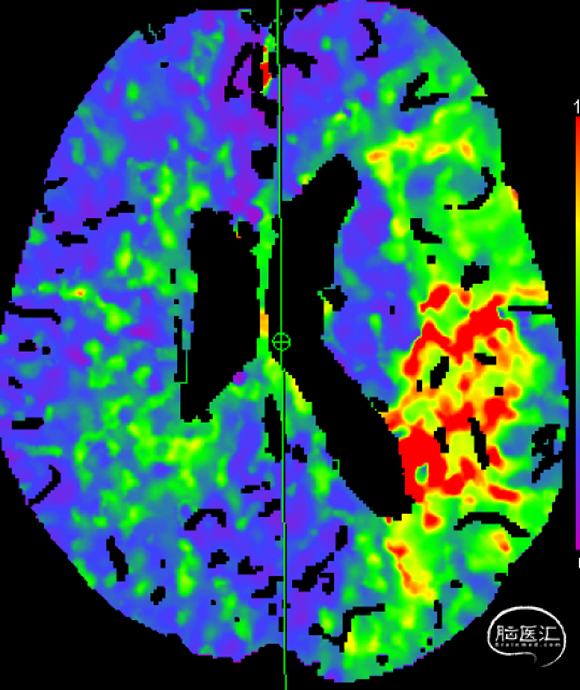

患者入院后(2-22 21:30PM)症状加重,部分混合型失语,右上肢肌力0级,右下肢肌力3级,右侧鼻唇沟变浅,NIHSS评分12分。(急诊CTP)。

患者老年女性,既往心房颤动病史。因“言语障碍及右侧肢体乏力29小时”入院。患者有明确的大血管闭塞,入院后患者症状加重,MRA提示左侧大脑中动脉闭塞,考虑进展性卒中,患者急诊CTP评估后考虑缺血半暗带大有血管内治疗指征,排除禁忌,拟急诊手术治疗。

患者急性起病,最初起病NIHSS评分3分,最初头颅MRA可见LM1大血管闭塞,但仍有血管残端,结合DWI图像,考虑血栓在分叉部未完全堵塞血管;但后来患者突然加重,考虑侧枝衰竭或血栓位移或二次心源性栓塞可能性大(有房颤病史),计划首先ADAPT抽吸,再Solumbra技术抽拉结合取栓治疗,视情况必要时补充技术。